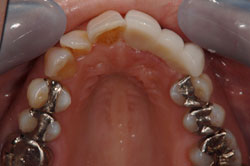

審美歯科症例 K.Kさん(44歳女性)

治療前

ジルコニアクラウンのブリッジで治療しました。

年齢・性別 44歳 女性

治療費 396,000円(税込)

治療期間 1ヵ月

通院回数 4回

リスク・注意点 ブリッジタイプは歯間ブラシを使ってください。